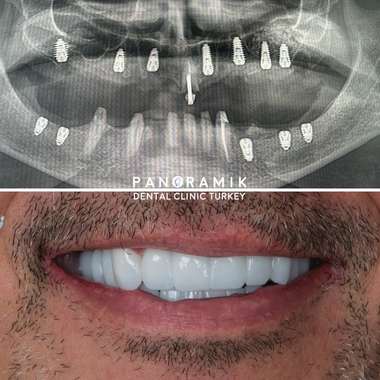

Zahnimplantate sind künstliche Zahnwurzeln, die eingesetzt werden, wenn Zähne fehlen. Sie dienen als Grundlage für den künstlichen Ersatz verlorener Zähne. Viele Menschen mit fehlenden Zähnen leiden unter funktionellen und ästhetischen Problemen. Implantate sind besonders hilfreich, wenn die letzten Zähne im Kiefer fehlen und eine festsitzende Prothese, wie eine Krone oder Brücke, nicht möglich ist.

Bei der Verwendung von Implantaten wird zunächst der zu behandelnde Bereich mit örtlicher Betäubung gemacht. Die Implantate werden anstelle des fehlenden Zahnes eingesetzt. Wird das Implantat anstelle eines zuvor gezogenen Zahnes eingesetzt, entsteht zusätzlicher Platz für das Implantat. Durch das Durchschneiden des Zahnfleisches wird ein kleines Loch geöffnet. Da diese Operation unter Narkose durchgeführt wird, sind keine Schmerzen zu spüren. Es dauert 4-6 Monate, bis das Implantat im Knochengewebe verwurzelt ist. Dieser Vorgang wird als Osseointegration bezeichnet. Mit implantierten Zähnen kann der Patient seinen bisherigen Komfort hinsichtlich Funktionalität und Ästhetik im Alltag wiedererlangen.

Der Prozess umfasst die erste Untersuchung, bei der die Mundstruktur mit Röntgen- und CT-Tomografie untersucht wird, sowie die Platzierung der Implantate.